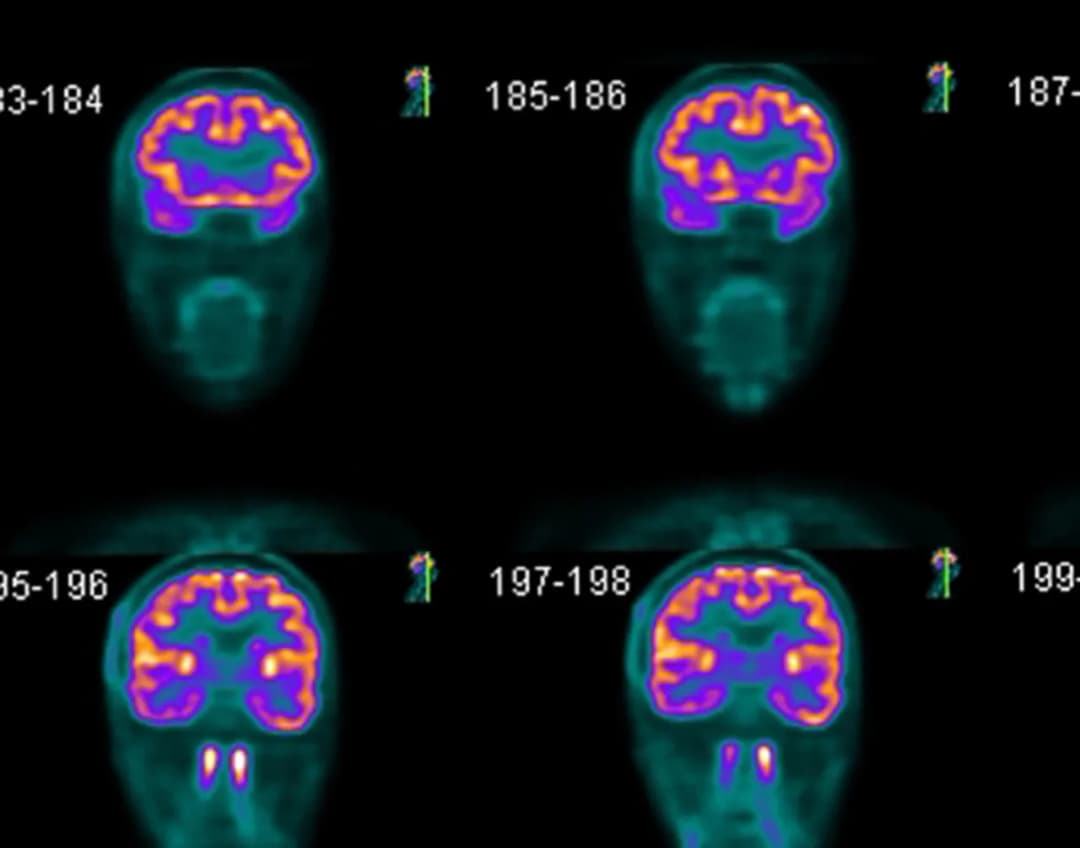

Szukasz placówki z najkrótszym czasem oczekiwania na badanie PET? Sprawdź aktualne terminy, porównaj ceny i znajdź najbliższą placówkę bez długich kolejek - zarówno na NFZ, jak i prywatnie.